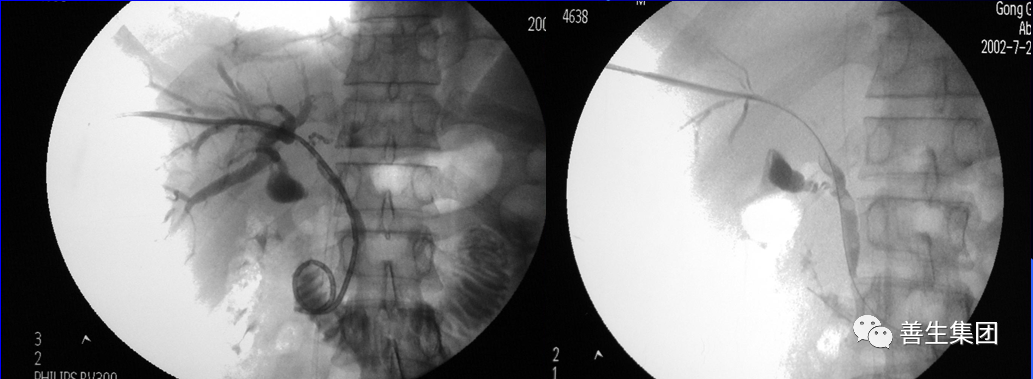

皮肤巩膜黄染伴皮肤瘙痒20余日,胰头MT。

胆管支架什么样子经皮肝胆管穿刺置管引流术(PTCD)及胆道内支架临床应用_https://www.jmylbn.com_新闻资讯_第14张

MIR和CT

胆管支架什么样子经皮肝胆管穿刺置管引流术(PTCD)及胆道内支架临床应用_https://www.jmylbn.com_新闻资讯_第15张

PTC造影+MIR胆道

胆管支架什么样子经皮肝胆管穿刺置管引流术(PTCD)及胆道内支架临床应用_https://www.jmylbn.com_新闻资讯_第16张

双导丝+左右肝管分别引流

胆管支架什么样子经皮肝胆管穿刺置管引流术(PTCD)及胆道内支架临床应用_https://www.jmylbn.com_新闻资讯_第17张

PTCD

胆管支架什么样子经皮肝胆管穿刺置管引流术(PTCD)及胆道内支架临床应用_https://www.jmylbn.com_新闻资讯_第18张